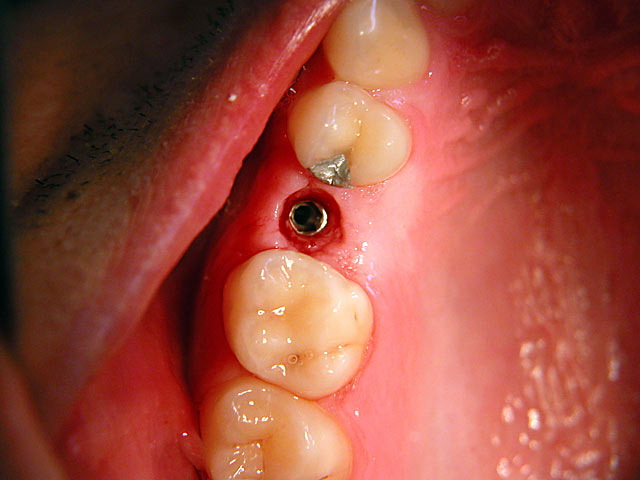

Die folgenden Patientenfälle sollen Ihnen einen Einblick in die Möglichkeiten der modernen Implantation geben.

Kurzimplantate und Sofort – Implantate: